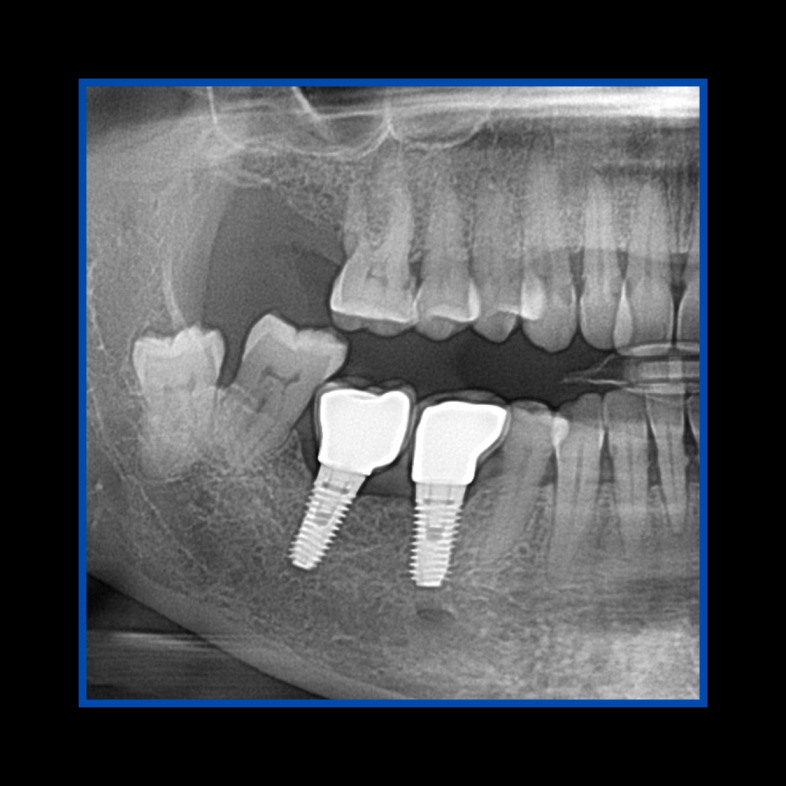

Ana sayfa > Klinik Vakalar > Diş çekiminin yıllar önce yapılmış olmasına bağlı olarak ince kemik varlığında implant ve kemik grefti uygulandı

Diş çekiminin yıllar önce yapılmış olmasına bağlı olarak ince kemik varlığında implant ve kemik grefti uygulandı